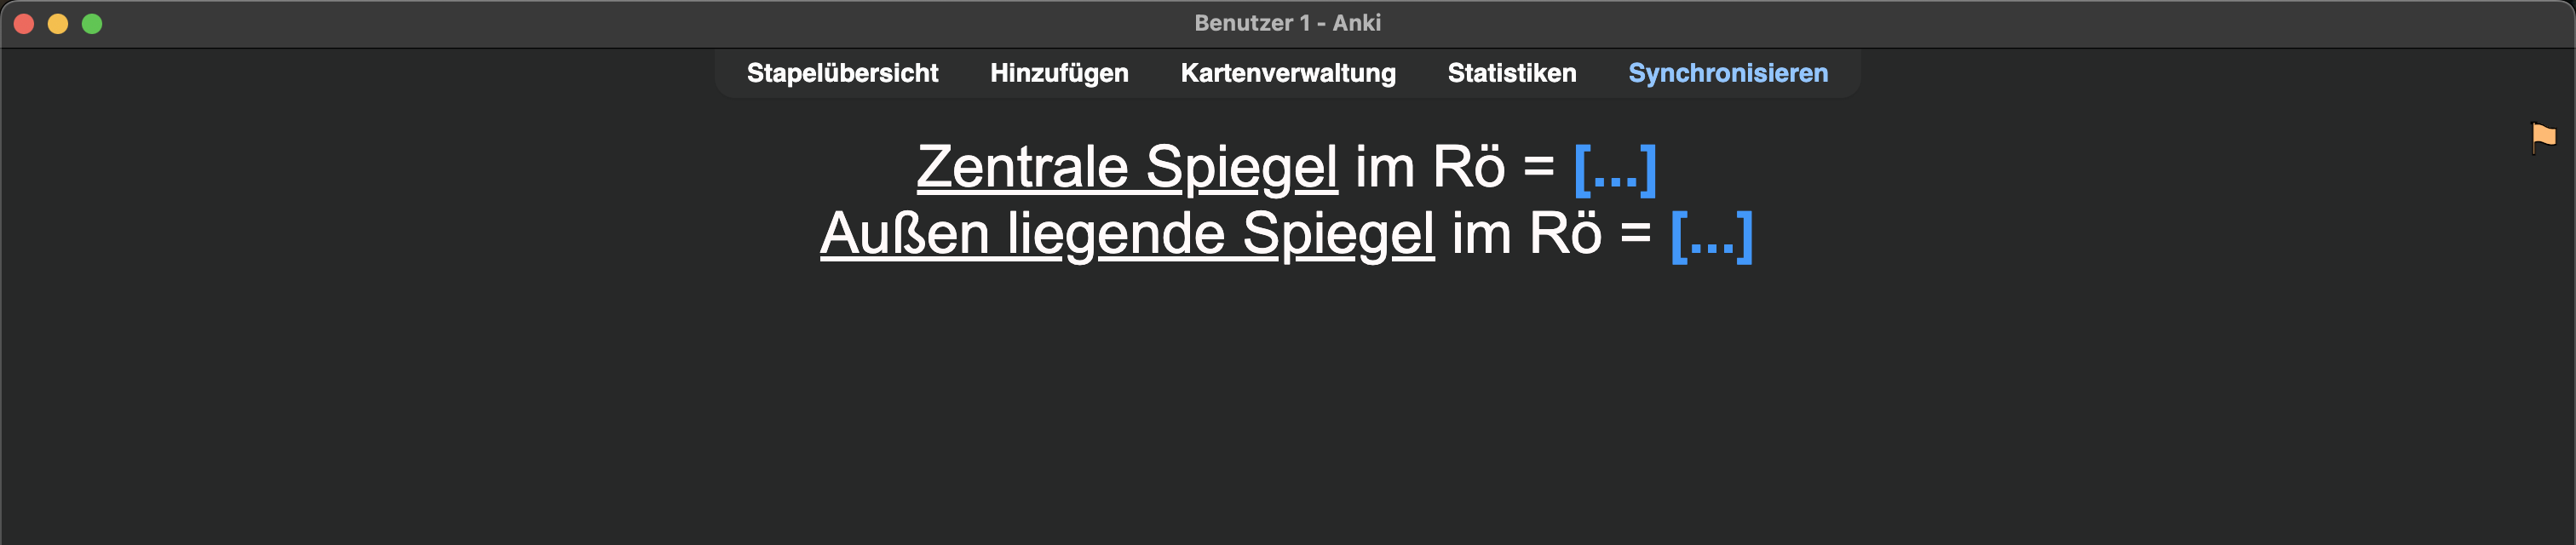

Ich konnte mir diese medizinische Information nur sehr schlecht merken:

Nach initialen erfolgreichen Wiederholungen (immer mit „Gut“ beantwortet) im weiteren Verlauf fünf Fehlversuche 😬. Also eine schlechte Karte! „Härter“ lernen bringt hier nichts; die Information ist einfach für mein Gehirn noch nicht appetitlich genug 🧀.

Also … Chunk🪓: